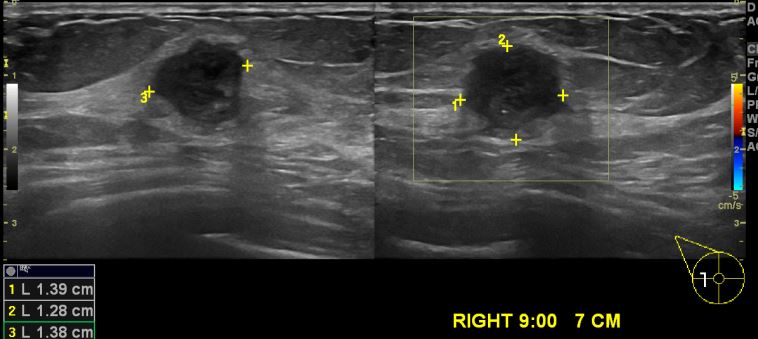

상기환자 건강검진상 이상 소견으로 내원하신 60대 여성분으로 우측 9시 방향에서7cm

떨어진 거리의 의심스러운 멍울 조직검사 시행하여 우측 침윤성 유관암 진단 되었습니다.